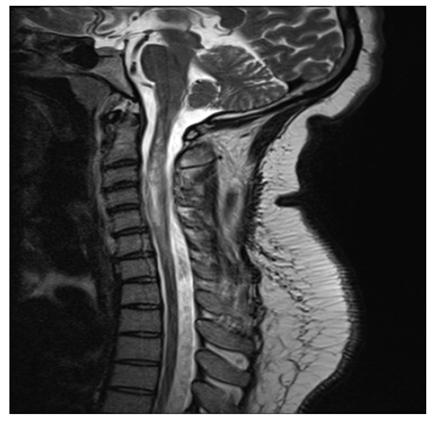

Q7: A 75-year-old woman with history of prior cervical spine decompression presented with progressive neck pain, asymmetric hand tingling, and neuropathic pain, followed by urinary incontinence and gait difficulty. Sagittal T2 weighted imaging likely shows?.